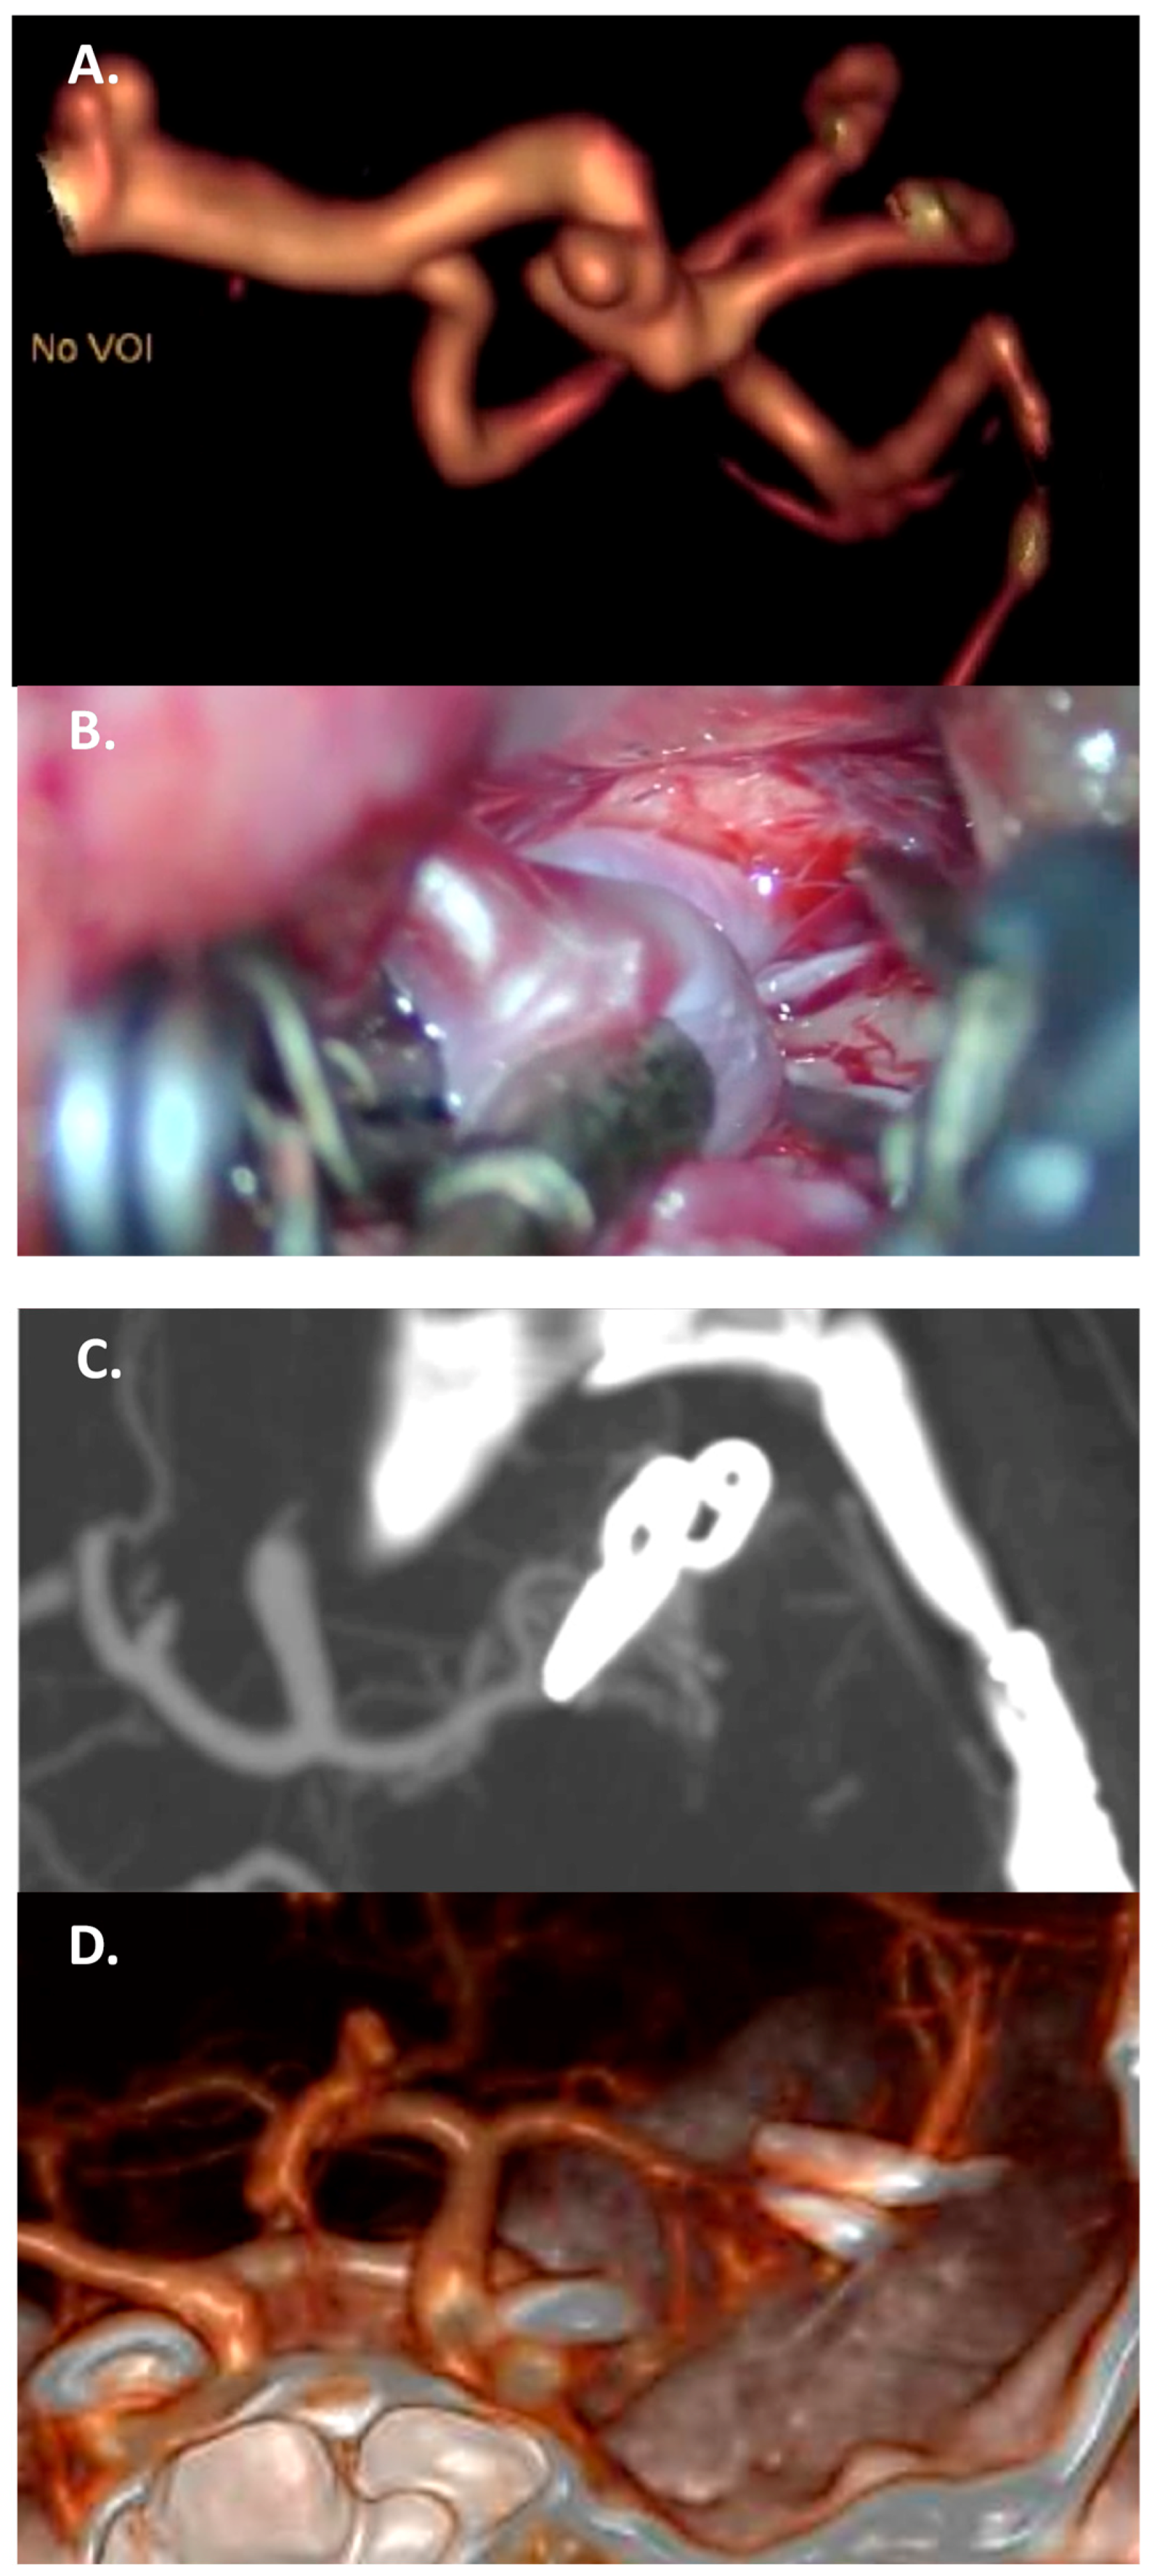

4.3.2. Vessels Branching from the Dome